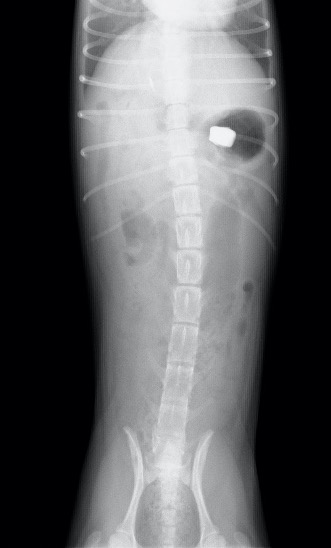

仰向けでのX線写真。

催吐直後。胃内は空になりましが、異物は胃内に留まっているのが分かります。